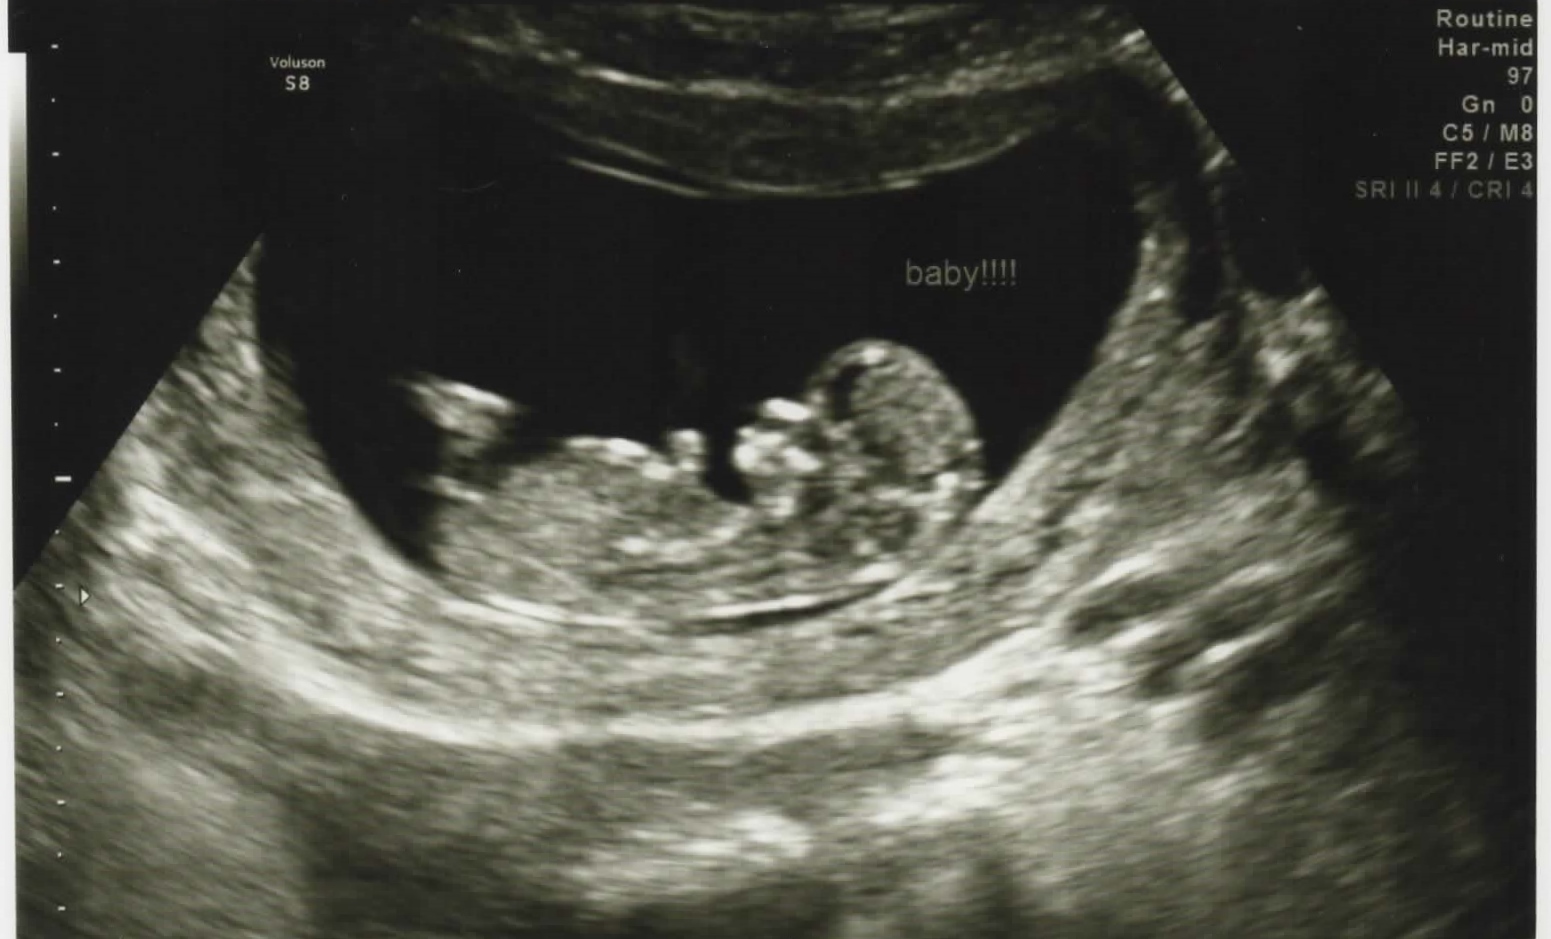

Nub guesses please!

Hi this is my first post here! I just had my first scan yesterday and the tech said she thinks it looks like a girl! We spent 10 minutes getting good shots of the nub! Anyways it seems kinda long and big? And im having some doubts =/ Attachment 17261Attachment 17262

In the second pic it looks like a split in the end of the nub..... Oh and 11 weeks 6 days!

is it normal for a girl nub to be so thick and long?

Girl- they do tend to be longer than boy nubs. It's very flat now but there is potential to rise since it's still early. Would guess girl though 60/40